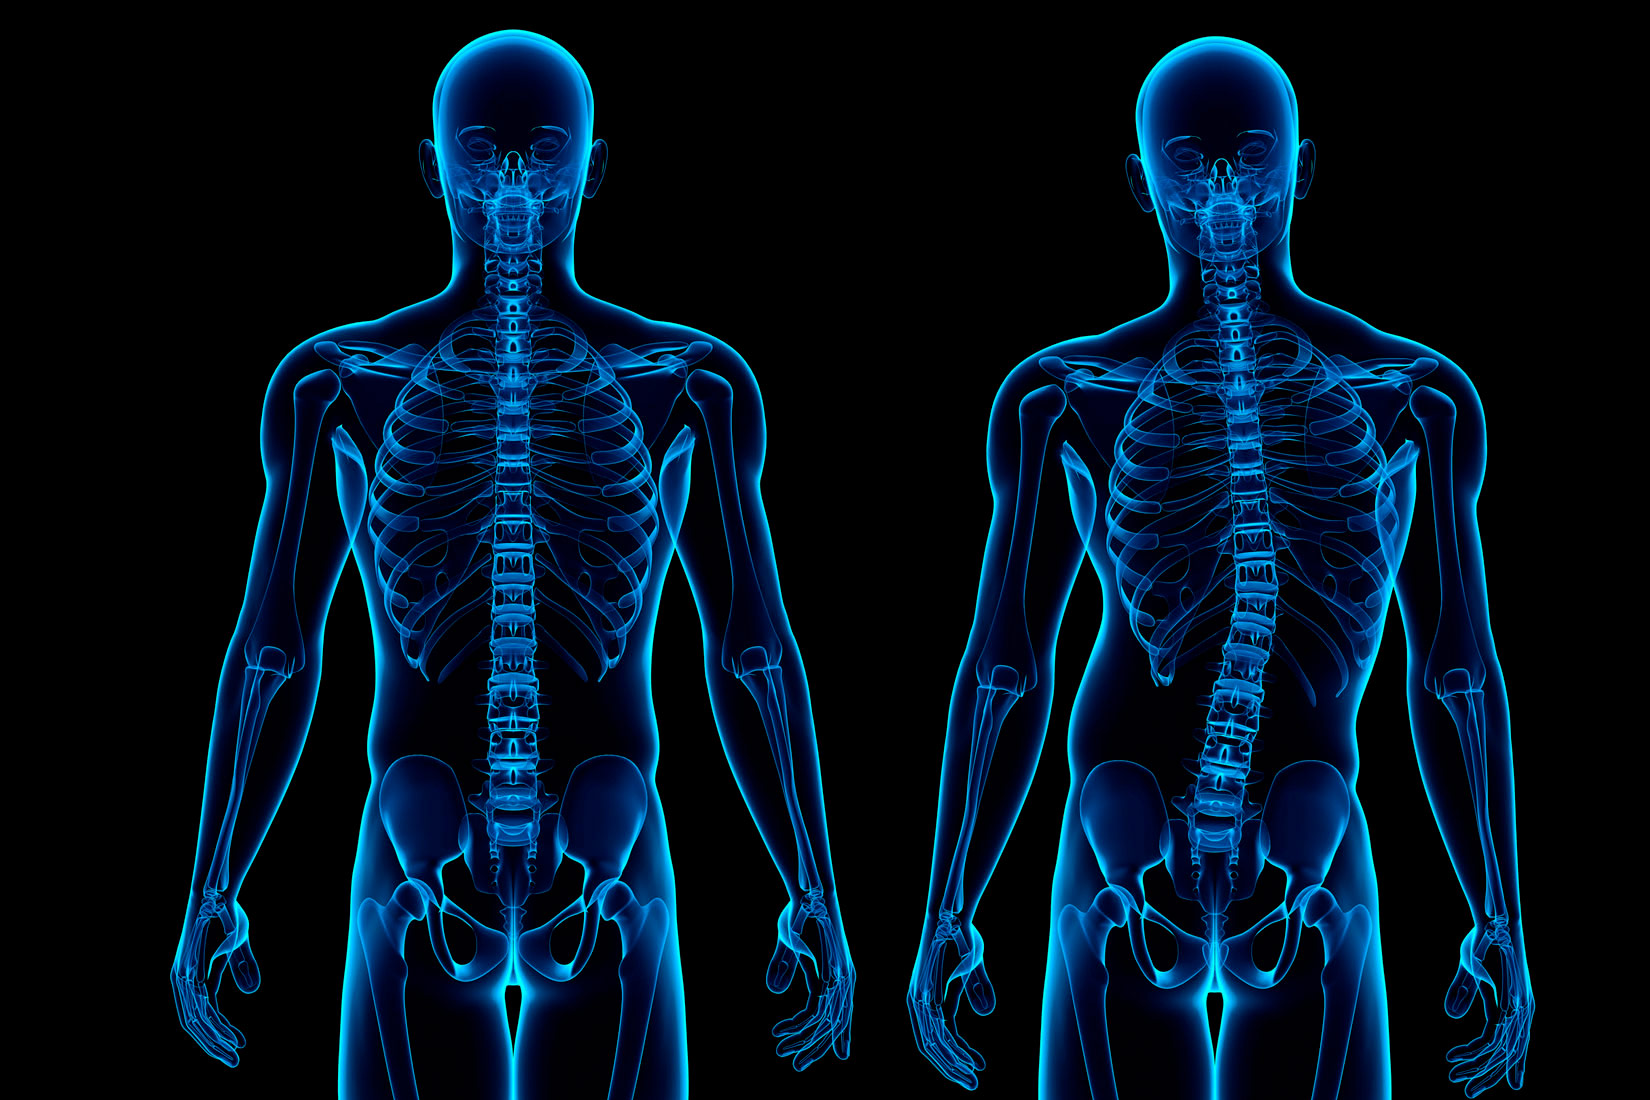

Kad skinemo sve, ostaje kostur

Čovjek u tijelu ima 206 kostiju.

One su povezane u cjelinu i čine kostur.

Kostur je podijeljen na tri cjeline:

Kostur čovjeka sastoji se od 206 kostiju povezanih u cjelinu.

Kralježnica nije ravna kao štap.

Ona je blago savijena u obliku dva slova S.

To joj omogućuje nošenje težine glave i vrata.